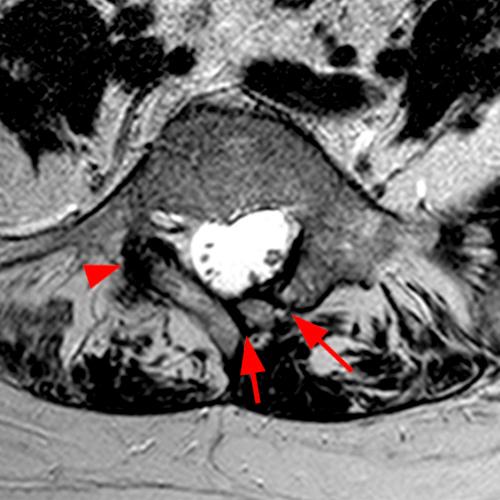

Case 1: T2-weighted axial (3A) and sagittal STIR (3B) sequences show marked cortical T2/STIR hyperintensity in the left pedicle of L5 surrounding a hypointense line (arrows) which begins at the inferior/medial margin of the pedicle and nearly completely traverses the pedicle.

Case 1: Acute left-sided pediculolysis